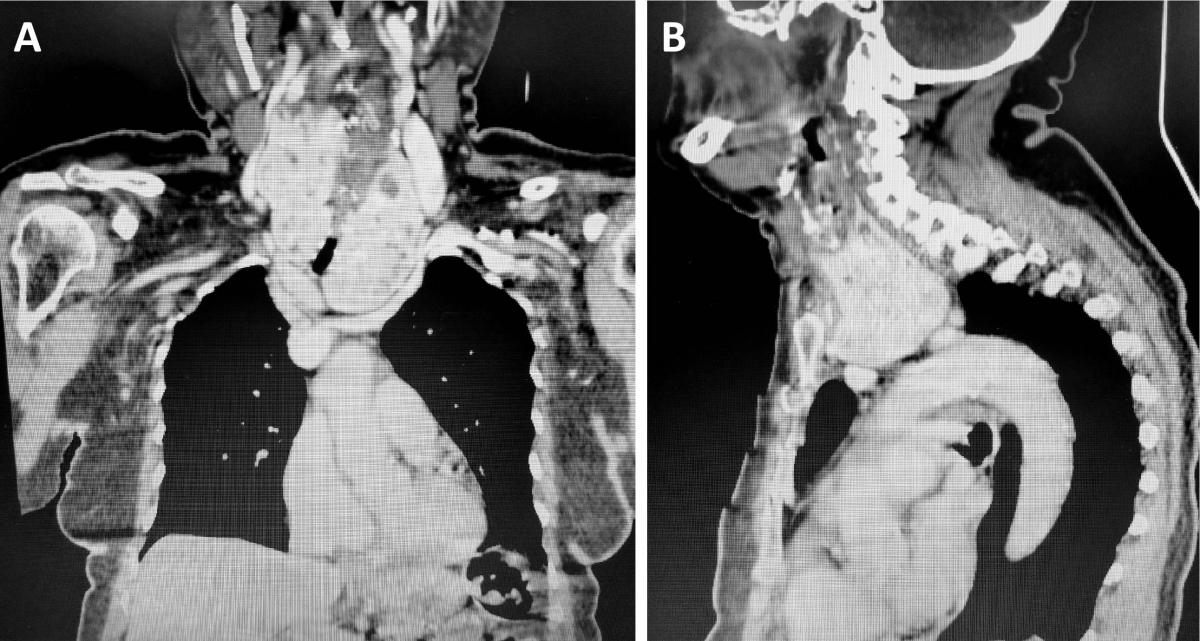

Figure 11. (A) Computed tomography of the neck and thorax (coronal plane) of a patient with a substernal goiter causing dysphagia and compression of aortic arch branches. One can see the enlarged cervical thyroid plunging into the mediastinum, the so called “plunging” or “diving” goiter. This is the most common type of mediastinal thyroid, also called secondary substernal goiter. The vascular supply is in the neck, chiefly from the inferior thyroid arteries. It is different from the mediastinal ectopic thyroid, which has no connection with the cervical gland and possess a distinct vascular supply that comes from intrathoracic vessels. (B) CT of the neck and chest (sagittal plane) of the same patient shown in panel A, with a substernal goiter (“diving goiter”). The enlarged cervical thyroid plunges into the mediastinum, “sitting” on the aortic arch branches. This patient had a history of cerebral vascular accident.